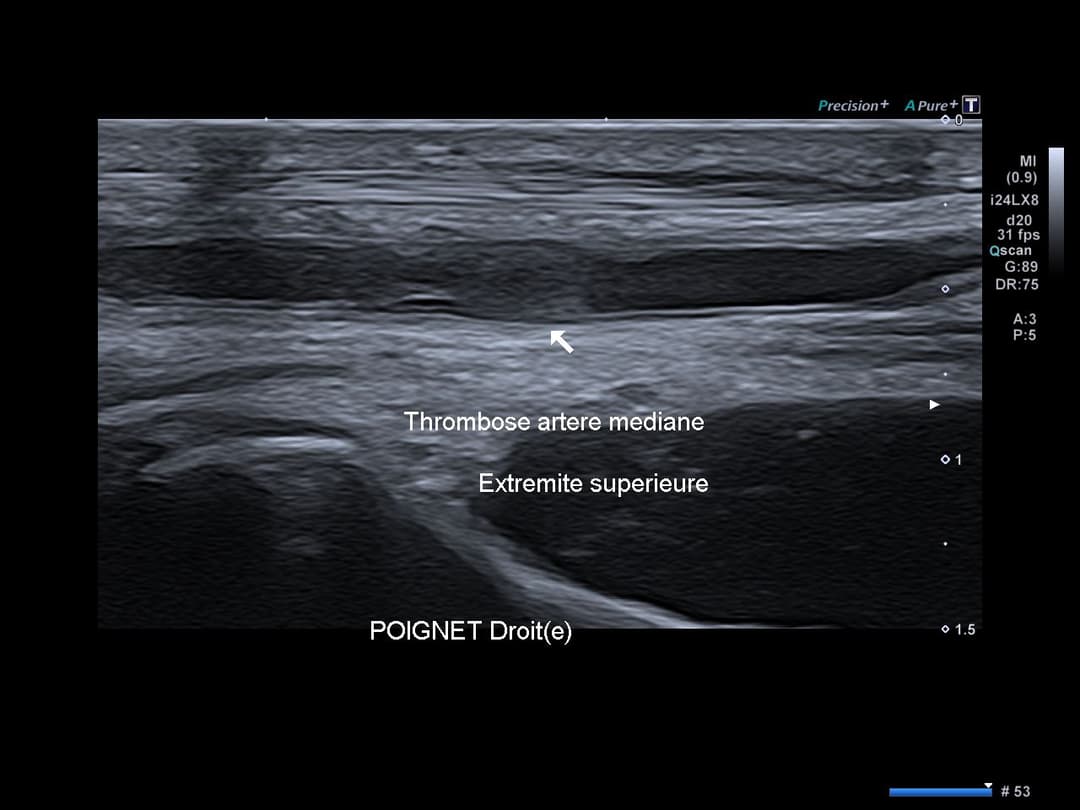

Matériel échogène endoluminale de l'artère médiane persistante du poignet droit, au niveau de son passage dans le canal carpien, traduisant une thrombose artérielle.

Accentuation de l'échogénicité des parties molles adjacentes traduisant un œdème réactionnel avec hyperhémie en Doppler couleur.